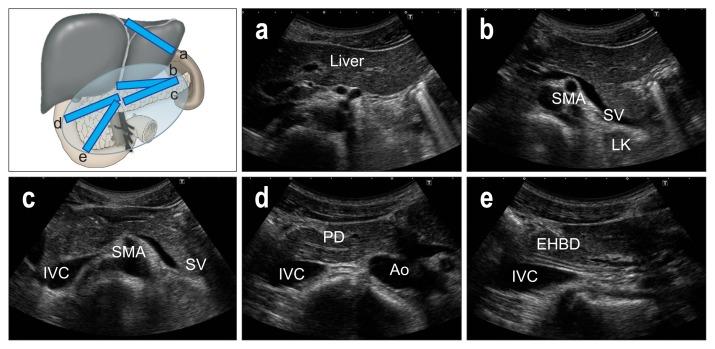

As ultrasound (US) is simple and less invasive than other imaging modalities, this technique is widely used for mass screening. However, visualizing the entire pancreas due to complicated anatomy, obesity and overlying gas can be difficult. US plays a key role in the diagnosis of pancreatic carcinoma (PC), of which tumors smaller than 10 mm (TS1a) and pancreatic carcinoma are expected to have good prognosis. To detect these forms of PC, main pancreatic duct (MPD) dilatation (3 mm or more) and pancreatic cysts (5 mm or larger) are US findings of high-risk individuals (HRIs), and these subjects should be observed periodically. Scanning maneuvers are also important for both screening for PC and follow-up of HRIs. As lesions in the groove area and ventral pancreas do not affect the MPD or extrahepatic bile duct, we should pay attention to these areas. Visualization of the tail is also challenging due to gas and stool in the alimentary tract. As the position of the pancreas changes depending on the body posture, and several different body positions should be employed, such as the right lateral decubitus, sitting, and upright positions, rather than only applying strong compression with the transducer. In cases with poor visualization, the liquid-filled stomach method is highly recommended.

由于超声(US)比其他成像方式简单且侵入性更小,因此该技术被广泛用于大规模筛查。然而,由于胰腺的复杂解剖结构、肥胖和上方气体的影响,很难对整个胰腺进行可视化。US 在胰腺癌(PC)的诊断中起着关键作用,其中直径小于 10mm(TS1a)和胰腺神经内分泌肿瘤的肿瘤预计具有良好的预后。为了检测这些形式的 PC,主胰管(MPD)扩张(3mm 或更大)和胰腺囊肿(5mm 或更大)是高危人群(HRIs)的 US 发现,这些患者应定期观察。扫描手法对于 PC 的筛查和 HRIs 的随访也很重要。由于沟区和胰头区域的病变不会影响胰管或肝外胆管,因此我们应该注意这些区域。由于消化道中的气体和粪便,尾部的可视化也具有挑战性。由于胰腺的位置随体位变化而变化,因此应采用几种不同的体位,如右侧卧位、坐位和立位,而不是仅用探头进行强力压迫。在可视化效果不佳的情况下,强烈推荐使用充满液体的胃法。